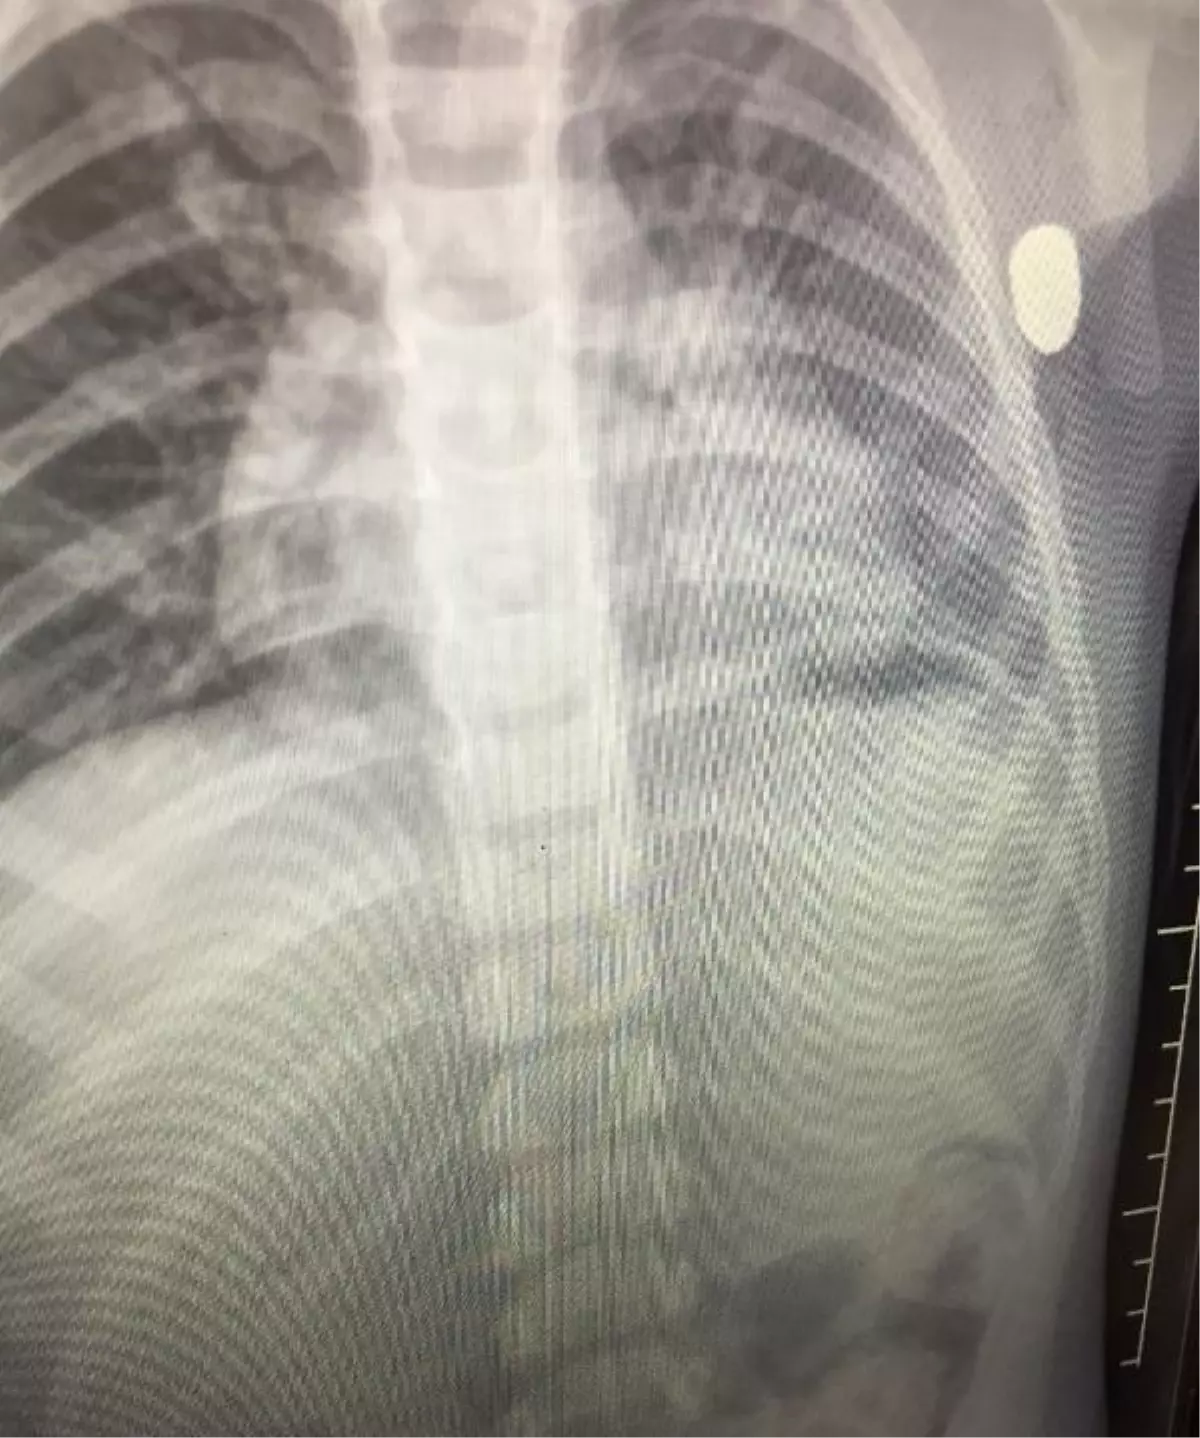

Olay saat 21.30 sıralarında ilçedeki Yeşilırmak Doğal Yaşam Parkı'nda meydana geldi. İlkadım ilçesinden ailesi ile birlikte geldiği parkta salıncakta sallanan Berkin Aydemir, aniden düştü. Aydemir'in kolunun alt kısmından kanlar geldiğini gören ailesi, durumu sağlık ekiplerine bildirdi. İhbar üzerine parka gelen sağlık ekiplerince ilk müdahalesi yapılan Aydemir, ambulansla Çarşamba Devlet Hastanesi'ne kaldırdı. Durumu ağırlaşan Aydemir, sevk edildiği kent merkezindeki Eğitim ve Araştırma Hastanesi'nde ameliyata alındığı öğrenildi. Tedavisi süren Aydemir'in maganda kurşununun hedefi olduğu, yorgun merminin de sol kolunun alt kısmından girip, göğsüne saplandığı tespit edildi. Soruşturma başlatan polis, silahı ateşleyen kişinin tespit edilmesi için çalışma başlattı.